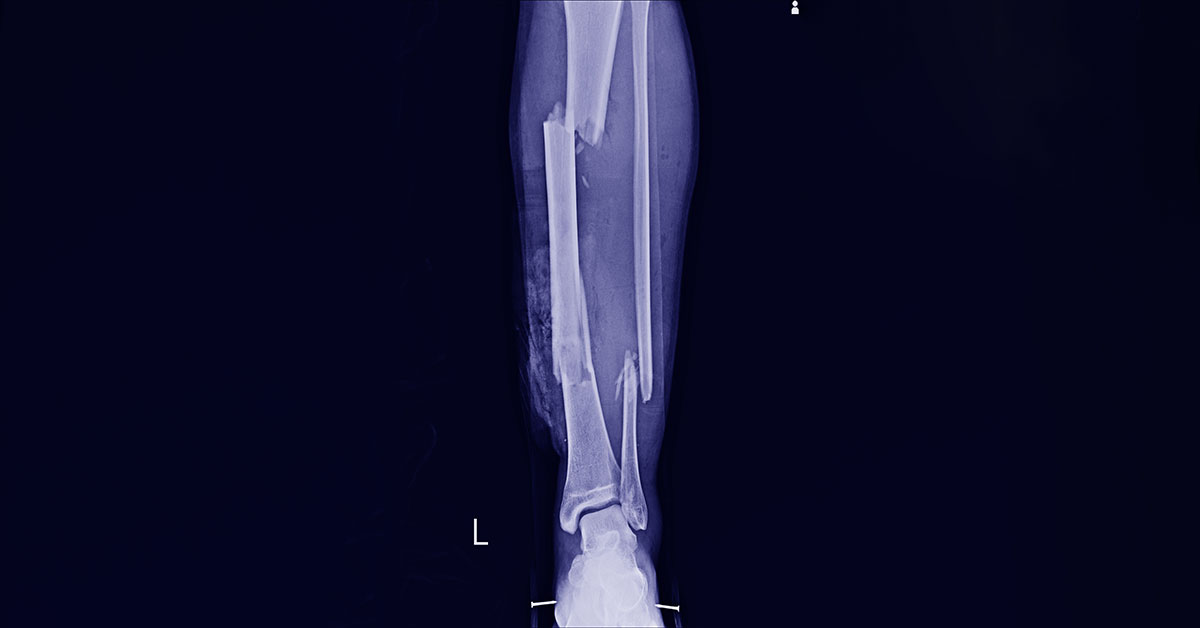

Segundo a Brigada, ao chegar no local deparou com a vítima com escoriações pelo corpo e suspeita de fratura de fíbula e tíbia e a mesma perdia muito sangue em consequência da fratura exposta na perna direita.

Nossa reportagem entrou em contato com Lucival Souza, coordenador da Brigada e ele disse que no hospital a equipe médica confirmou as faturas e que estava regulada para ser transferida para outra unidade de saúde mais avançada.